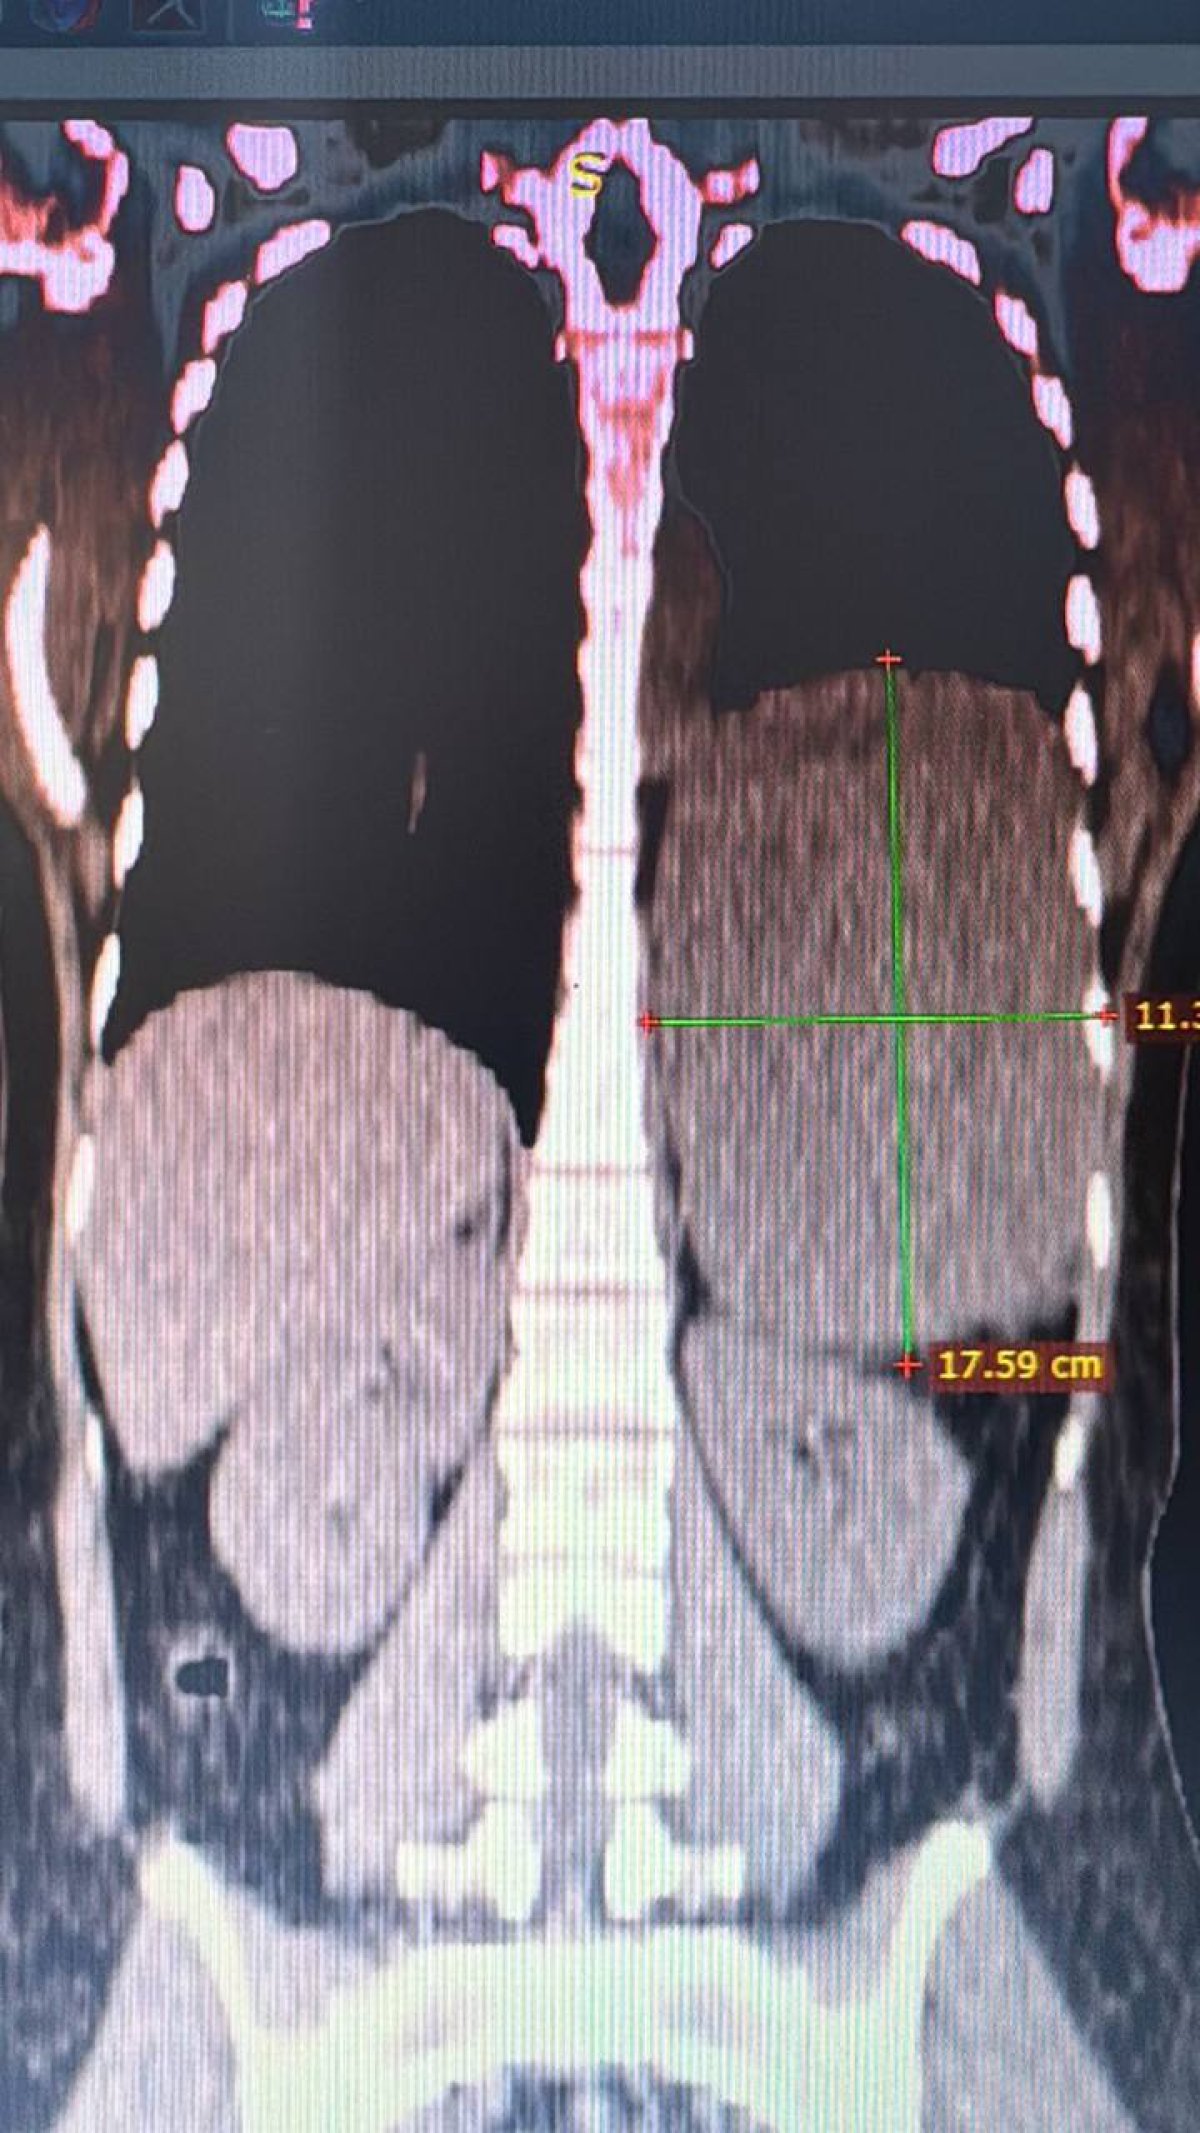

Как рассказали врачи, компьютерная томография органов брюшной полости показала левосторонний экссудативный плеврит и жидкостное образование в забрюшинном пространстве под диафрагмой. А гистологическое исследование подтвердило злокачественный характер опухоли размером 20 на 12 сантиметров. Она проросла по обе стороны диафрагмы.